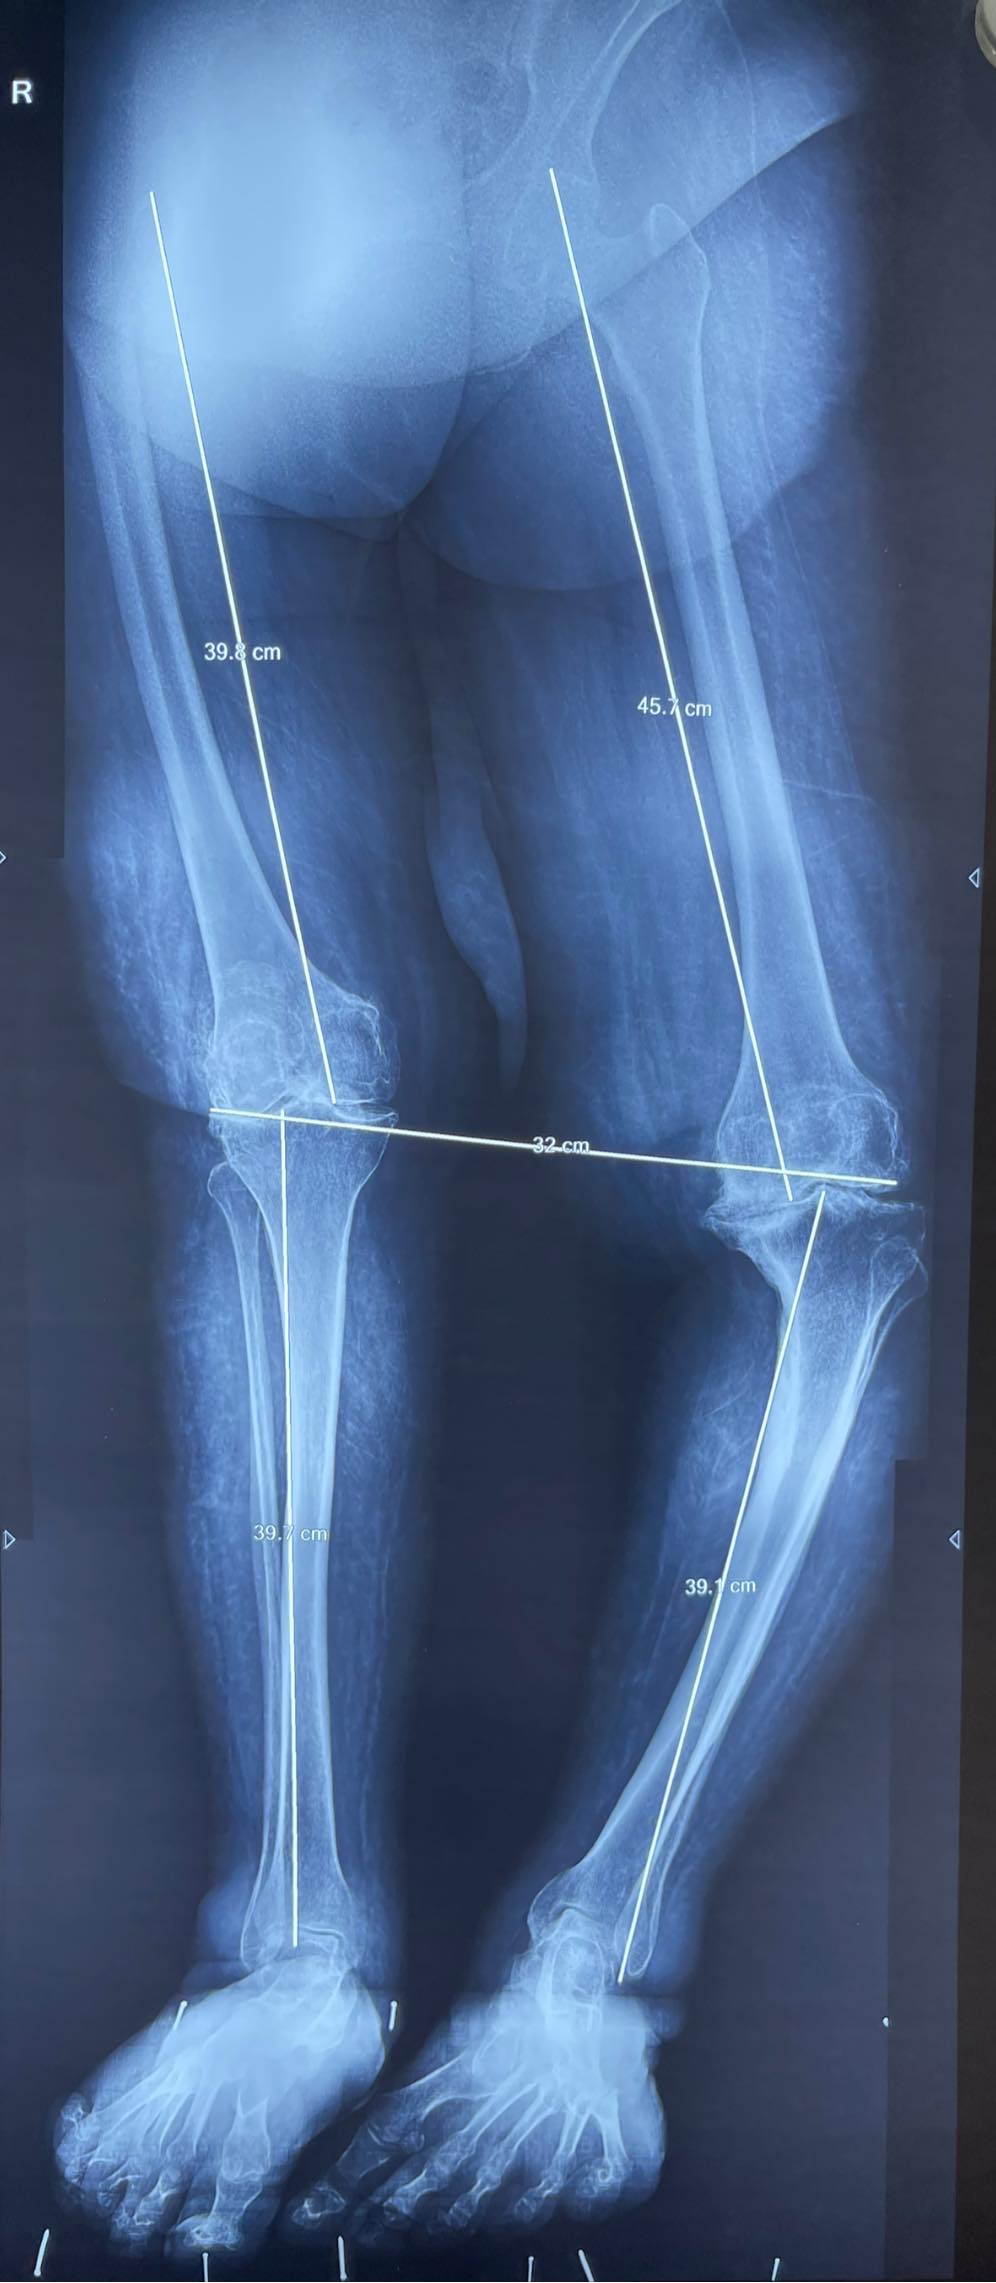

A 57-year-old female with ol malunited tibial plateau fracture and OA knee. In such cases just replacing the knee joint will not suffice as the deformed leg will cause continued pain and eventual failure of the surgery. The osteotomy straightens the leg deformity which is stabilized with this long stem prosthesis and outside recon plate.